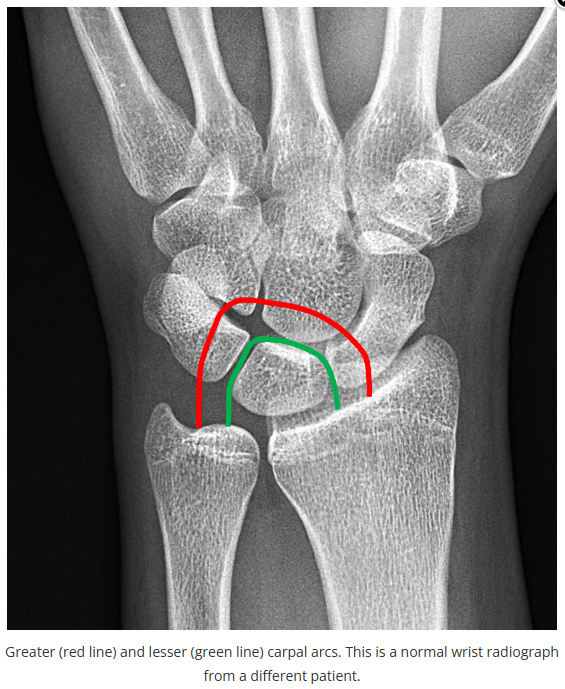

今天是腕部与手的X线片。所有X线片都

带有标注和说明

,可以选择长按图片,

自动翻译相关说明